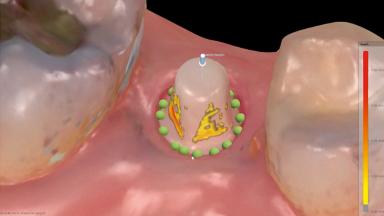

Guided Immediate Placement of a Ceramic Implant in a Maxillary Right Second Premolar and Immediate Restoration with a CAD/CAM-Fabricated Provisional Crown

With this case, André Chen highlights the importance of the correct 3D positioning of monotype ceramic implants placed immediately in a single-tooth situation. One-piece implants have biological advantages but placing them in the correct prosthodontic position can be a challenge.